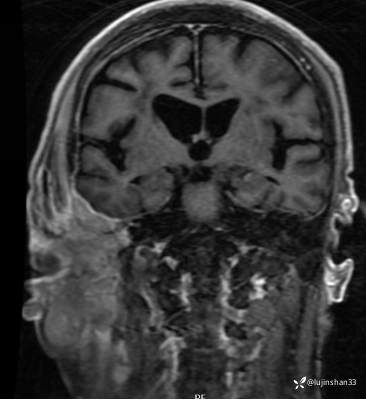

MRI: